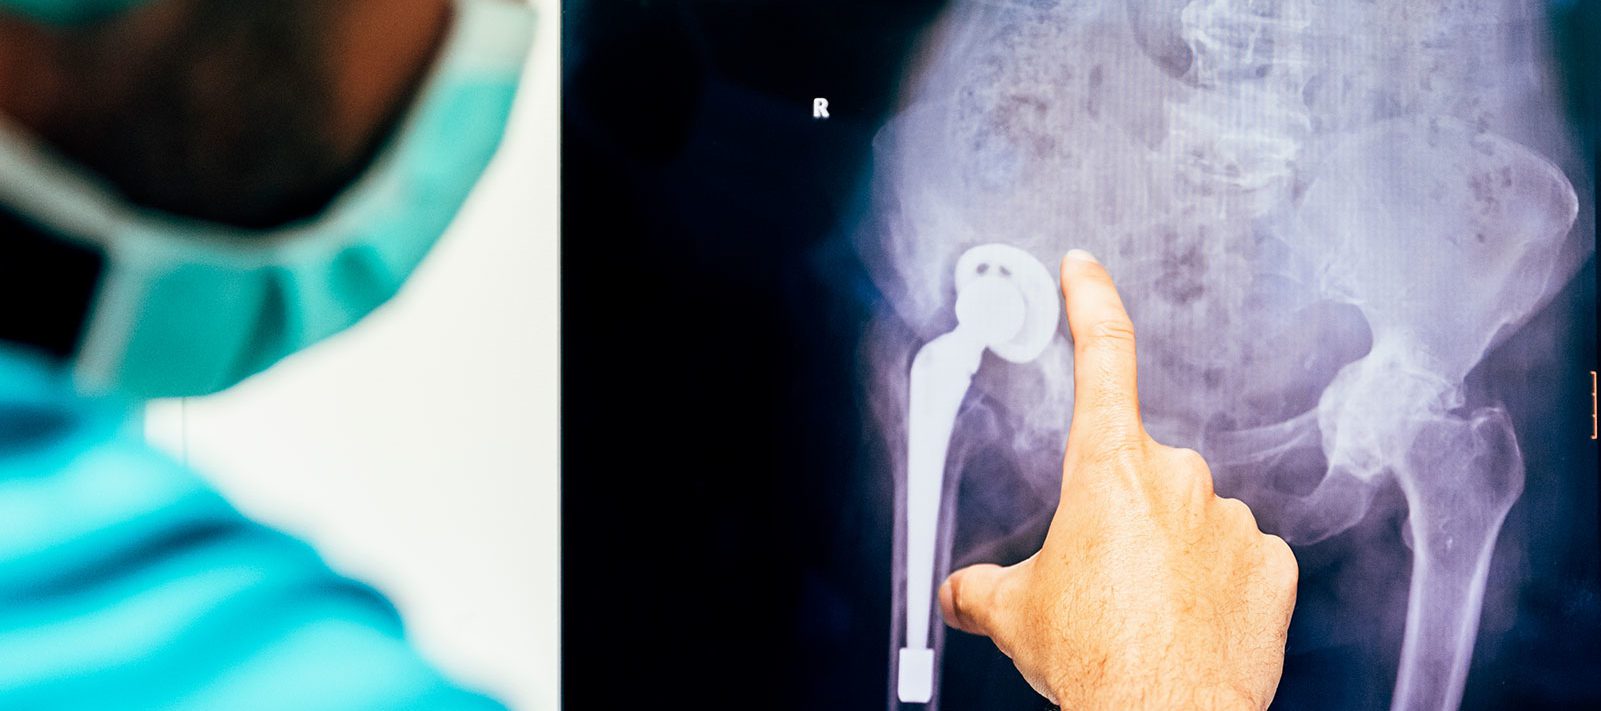

Your Hip Implant? Here’s Key Information You Need

Patients worldwide have complained of severe pain and other debilitating side effects after certain metal-on-metal hip implants. If you’re suffering from a condition such as metallosis after receiving an implant, we can tell you if you may have a claim for compensation.

Smith & Nephew has joined other hip implant manufacturers in removing certain metal-on-metal hip implants from the market after complaints over debilitating side effects, such as severe pain and toxic metal poisoning caused by debris eroding from the implants, known as metallosis.

Two Smith & Nephew hip implants – the Modular SMF system and the Modular REDAPT system – were recalled in 2016 in what has been a string of worldwide recalls over the last several years involving metal-on-metal hip implants.

Metal-on-metal hip implants can shed metal particles into the surrounding tissue, enter the bloodstream, and may potentially lead to toxic metal poisoning. This metal poisoning, known as metallosis, is caused by the accumulation of tiny metal particles in the tissue, joints, and blood.